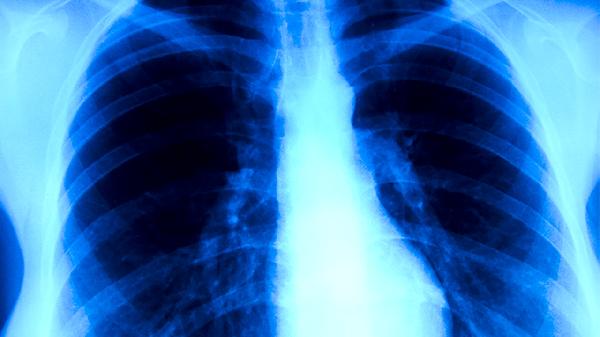

肺结核患者单纯依靠中药通常难以彻底治愈,需以抗结核西药为主、中药为辅进行综合治疗。肺结核是由结核分枝杆菌感染引起的慢性传染病,规范治疗主要依赖异烟肼片、利福平胶囊等抗结核药物,中药可辅助缓解症状或减轻药物副作用。

肺结核患者应坚持高蛋白、高维生素饮食,每日进行30分钟温和有氧训练如太极拳。居住环境保持通风干燥,餐具需定期煮沸消毒。治疗期间每月复查胸部CT和痰涂片,出现视力模糊、关节痛等异烟肼副作用时及时就医调整方案。密切接触者应进行结核菌素皮肤筛查。